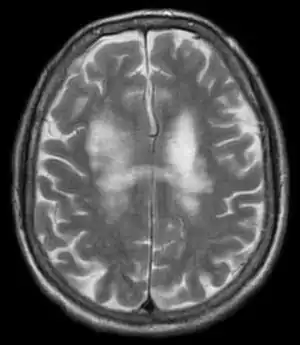

| T2-weighted MRI showing progressive multifocal leukoencephalopathy | |

PML is diagnosed in a patient with a progressive course of the disease, finding JC virus DNA in spinal fluid together with consistent white-matter lesions on brain magnetic resonance imaging (MRI); alternatively, a brain biopsy is diagnostic[1] when the typical histopathology of demyelination, bizarre astrocytes, and enlarged oligodendroglial nuclei are present, coupled with techniques showing the presence of JC virus.[12]

Characteristic evidence of PML on brain CT scan images are multifocal, noncontrast enhancing hypodense lesions without mass effect, but MRI is far more sensitive than CT.[12] The most common area of involvement is the cortical white matter of frontal and parieto occipital lobes, but lesions may occur anywhere in the brain, such as the basal ganglia, external capsule, and posterior cranial fossa structures such as the brain stem and cerebellum.[12] Although typically multifocal, natalizumab-associated PML is often monofocal, predominantly in the frontal lobe.[12]

High signal intensity lesion of white matter of dorsal right frontal lobe/right frontal operculum